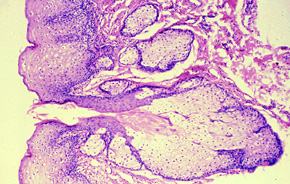

Fordyce Spots = بقع فوردايس